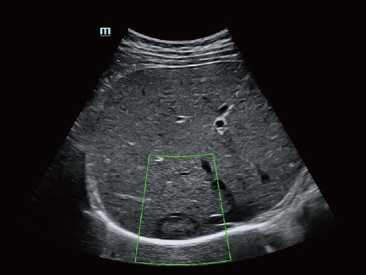

Since the company was founded, Mindray has been continuously exploring new ways to improve diagnostic confidence. Powered by the most revolutionary ZONE Sonography? Technology, Resona 7ŌĆÖs new ZST+ platform brings ultrasound image quality to a higher level by zone acquisition and channel data processing.

As well as the premium level image quality, Resona 7 also enhances clinical research capabilities with the revolutionary V Flow for vascular hemodynamic evaluation, and the most intelligent plane acquisition from 3D datasets for fetal CNS diagnosis. Combining the most intuitive gesture-based multi-touch operation and all the essential clinical features, Resona 7 is truly leading new waves in ultrasound innovation.